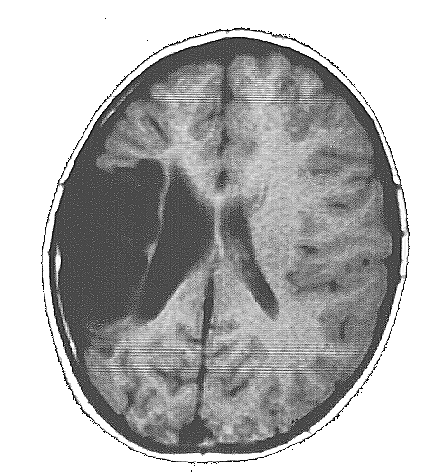

As crianças ARM e KTG são portadoras de lesões cerebrais denominadas Esquizencefalia (Fig. 5 e 6), que são decorrentes de distúrbios no processo embriogênico, que ocorrem no primeiro trimestre da gravidez. As lesões no indivíduo ARM se localizam no lobo frontal esquerdo e incluem também a ausência do septo pelúcido. Já a criança KTG tem as lesões localizadas no lobo parietal direito e também mostra sinais de comprometimento do hipocampo direito.

As lesões do indivíduo WA são do tipo Leucomalácia Multicística e se localizam principalmente no lobo parietal esquerdo. As lesões decorreram de problemas anóxicos perinatais, causados por problemas que a mãe experimentou alguns dias antes do parto. WA e ARM são canhotos e hemiplégicos à direita, e apresentaram atraso no desenvolvimento psicomotor. KTG é destra e tem hemiplegia à esquerda, apresentou também, atraso do desenvolvimento psicomotor.

Os MAREs de todos os indivíduos mostram uma atividade cerebral coerente com a lesão encontrada nas correspondentes MRIs. Assim, por exemplo, ARM tem uma lesão frontal esquerda na MRI, que está associada á um silêncio funcional nas derivações frontais esquerda nos seus MAREs (Fig. 5). Já o indivíduo WA tem uma lesão que se localiza predominantemente no lobo parietal esquerdo, que está associada a uma ausência de atividade nas derivações C3 e P3 nos seus MAREs mostrados na fig. 5. Finalmente, a lesão de KTG se localiza principalmente no lobo parietal direito, que se reflete nos correspondentes MAREs, por uma diminuição da ativação, principalmente, nas derivações P4 e T6.

A criança ARM tem uma lesão que compromete extensamente seu lobo frontal esquerdo, mostrando uma hemiplegia à direita e dificuldades de fonação. Sua lesão afeta também o fascículo arcuado, de modo que as áreas temporais esquerdas estão isoladas do pouco córtex frontal esquerdo que restou nesse indivíduo.

Corroborando esses achados, os MAREs apresentados na fig. 5, mostra uma boa ativação de áreas frontotemporais no hemisfério direito, quando do processamento da informação verbal no jogo de charadas. Parece, portanto, que a capacidade lingüística dessa criança é suportada pela ação do hemisfério não dominante. Aceita essa premissa, os MAREs mostrados na fig. 5 para esse indivíduo, demonstram claramente um alocação da função verbal no hemisfério direito; isto é, mostram um caso típico de plasticidade neural induzida por uma lesão congênita. Outros autores, por exemplo Graviline et al., 1998; reportam o sucesso de realocação de funções com a precocidade da lesão.

As lesões de WA comprometem fundamentalmente o lobo parietal e parte do lobo frontal esquerdos. Mais uma vez, o fascículo arcuado parece estar lesado. Outra vez, tem-se o isolamento entre o lobo temporal e as áreas frontais no hemisfério esquerdo. WA é uma criança que tem uma hemiplegia direita e dificuldades articulatórias. Entretanto, é também capaz de uma boa compreensão da linguagem falada, comprovada pelo seu bom rendimentos nos jogos de ordenação, memorização, interpretação e reconstrução. Um fato marcante em sua linguagem é a ausência do uso das palavras funcionais: artigos, preposições, etc. Esse fato está de acordo com o comprometimento córtex frontal esquerdo observado neste indivíduo (pe, Pinker, 1995; Rocha, 1999).

Os MAREs apresentados na fig. 5 para o indivíduo WA, mostram claramente uma redução da atividade nas derivações temporoparietais esquerda, compatível com a lesão estrutural observada na MRI. Uma vez mais, há um isolamento do lobo temporal em relação ao frontal, no hemisfério esquerdo. Outra vez, observa-se uma compensação desse isolamento, por um aumento do envolvimento do hemisfério direito no processamento da informação verbal.